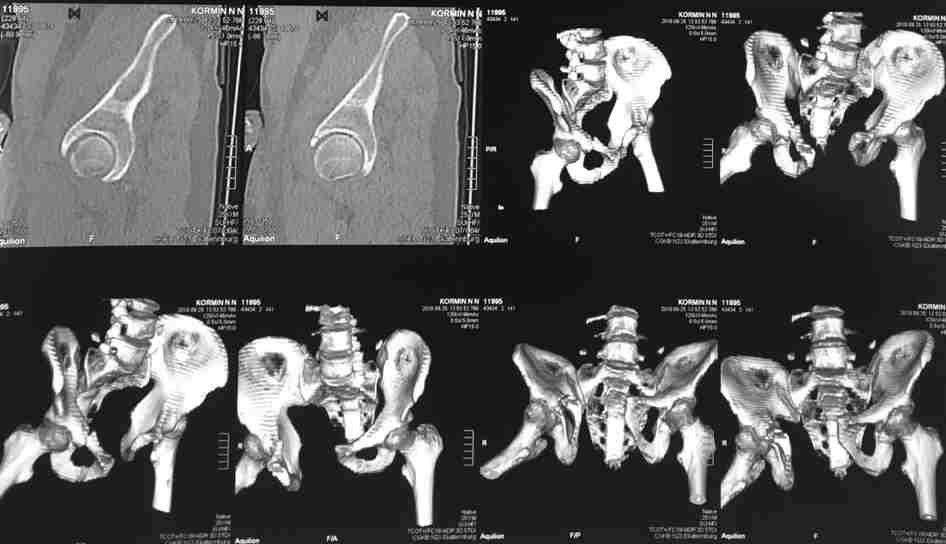

Молодой парень, без соматики. Сейчас чуть больше 2-х нед после операции, швы сняты, мочится сам. Был тяжелый, после операции дней 10 пытался выполнить лежа поперечный шпагат (успешно, так и лежал большей частью, может быть из-за обширной гематомы промежности). Репозиция не идеальная, но фиксация довольно надежная, за 2 нед ничего не "разъехалось". Сейчас пришел в ум. Когда по-вашему можно дать нагрузку и на какую ногу или на обе? Или вообще подскажете программу реабилитации.PS Заранее извиняюсь за качество снимков, до не делали (body scan), если не видно - то - полные разрывы КПС с двух сторон. после КТ сломался. Неврологии вроде бы нет.